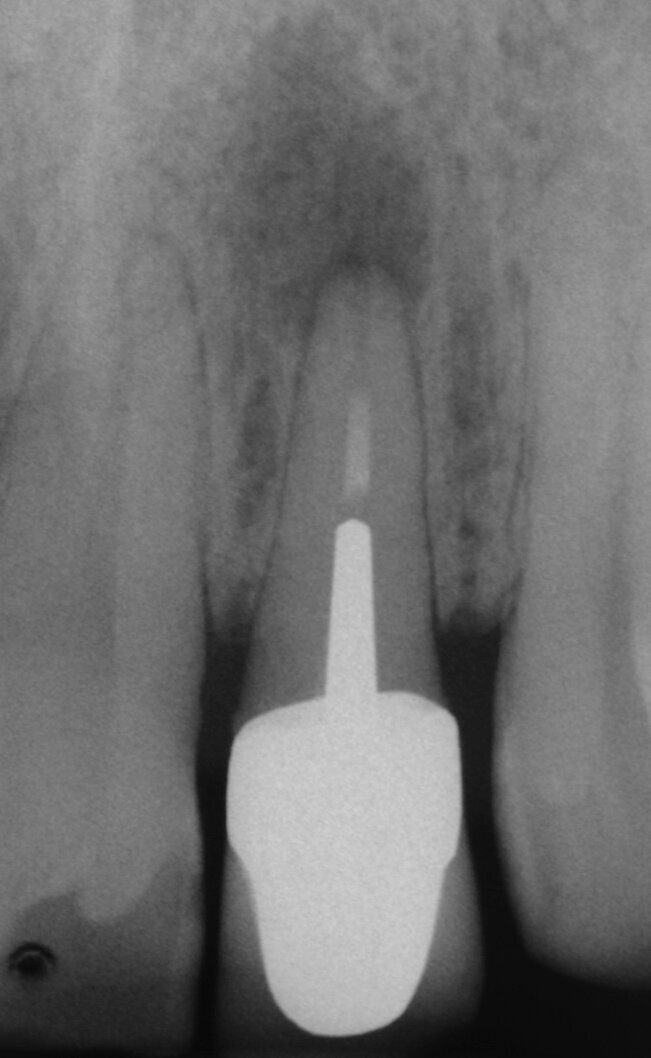

Fig. 2a: (a) Endodontically treated tooth with fistula. (b) After retreatment, the tooth showed an open apex. (c) MTA application with the MAP System and PD MTA White. Condensation of the MTA with pluggers (d) or paper points (e). (f) MTA plug. (g) Post-op radiograph showing the MTA plug and the reconstruction with a fibre post.

Fig. 2g: (a) Endodontically treated tooth with fistula. (b) After retreatment, the tooth showed an open apex. (c) MTA application with the MAP System and PD MTA White. Condensation of the MTA with pluggers (d) or paper points (e). (f) MTA plug. (g) Post-op radiograph showing the MTA plug and the reconstruction with a fibre post.

In order to prevent extrusion of root canal filling material in immature teeth with open apices, MTA is used as an apical plug. The results of many studies have shown that MTA induced apical hard-tissue formation more often and its use was associated with less inflammation than with other test materials (Figs. 2a–g).[4]